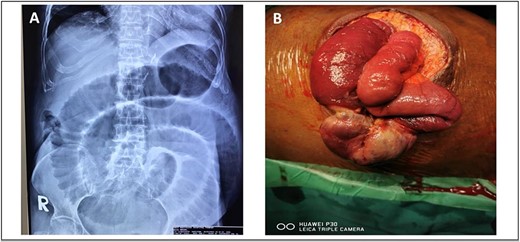

She was presented with an umbilical swelling for the past 1 week which had become painful for the past 2 days, associated with vomiting and unable to pass flatus and bowel motion. On examination, her vitals were normal. Per abdomen, there was 4 × 4 cm swelling at umbilicus with redness and skin changes. Plain abdominal radiograph showed dilated small bowel (Fig. 4A). Her blood parameters showed leukocytosis with white cell counts of 20, haemoglobin of 15, acute kidney injury with urea of 17, and creatinine of 154. Arterial blood gas was normal and no acidosis. The provisional diagnosis was strangulated paraumbilical hernia.

(A) Plain abdominal radiograph showed dilated small bowel (B) intraoperative finding of unhealthy sloughy small bowel segment in the hernia sac and pus was present.

We discussed with patient and her relative regarding the option of anaesthesia either local or general anaesthesia. They agreed and consented for local anaesthesia since it has the least complications and aware of conversion to general anaesthesia if the former method failed to work. We proceeded with the surgery under local anaesthesia and monitored sedation with the help of an anaesthesiologist. We did an infraumbilical transverse incision over the hernia and found small bowel ischemia within the hernia sac with pus (Fig. 4B). The hernia defect was 3 × 3 cm. Ten centimeters of segment small bowel was resected with primary side to side bowel anastomosis using linear stapler 75 mm. The hernia defect is primarily closed with nonabsorbable polypropylene suture. The skin was left open for wound dressing. She recovered slowly from surgery and was able to go home on Day 7 post-operation.